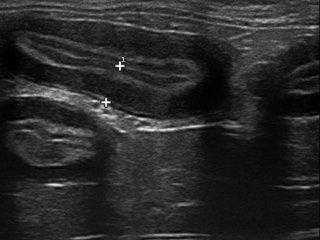

L’échographie est la technique de choix pour effectuer les suivis de SUB (« subcutaneous ureteral bypass ») en cas d’obstruction de l’uretère.

Grace à l’échographie, les lésions peuvent être ciblées et ponctionnées à l’aiguille fine. L’épaisseur de l’aiguille est la même que pour les prises de sang.

Si nécessaire, une plus grosse aiguille peut être utilisée afin de réaliser des biopsies échoguidées.